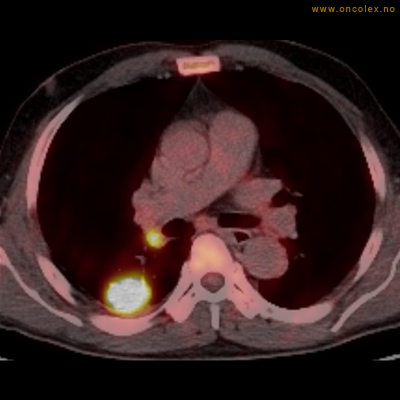

Vev som tar opp mer radioaktivt stoff, synes som hvite områder som lyser opp mer i forhold til annet vev som tar opp mindre sukker.

Adenokarsinom distalt i spiserør. Fysiologisk opptak i hjertemuskulatur.

Adenokarsinom langt nede i spiserøret.

Spredningssvulster til lever med sentral nekrose.